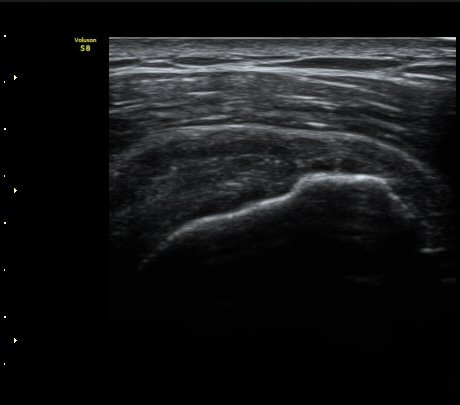

ÃÊÀ½ÆÄ °Ë»ç

À̵ιڱ٠Ⱦ´Ü¸é°Ë»ç¿¡¼­ Á¤¸Æ³¶ÀÇ ºÎÁ¾ÀÌ °üÂûµÊ(±×¸² 1).